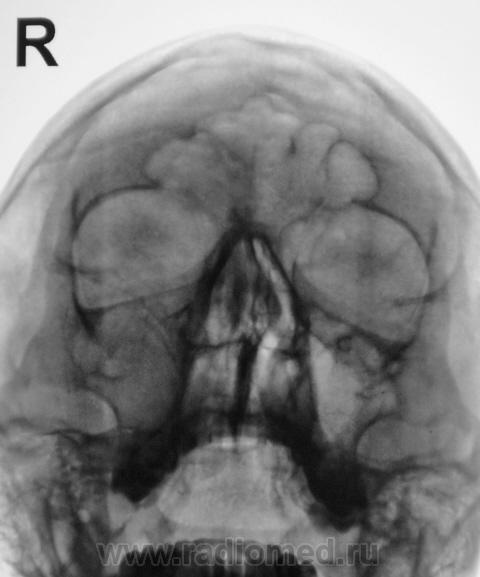

2 срез.

я не вижу четко стенок в.челюстной пазухи справа - атрфия от давления? может мукоцеле?

ассиметрия есть..